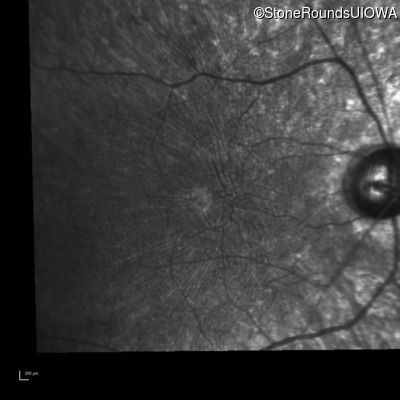

Infrared Fundus Photograph - Right - 5/180 sc

Exemplar